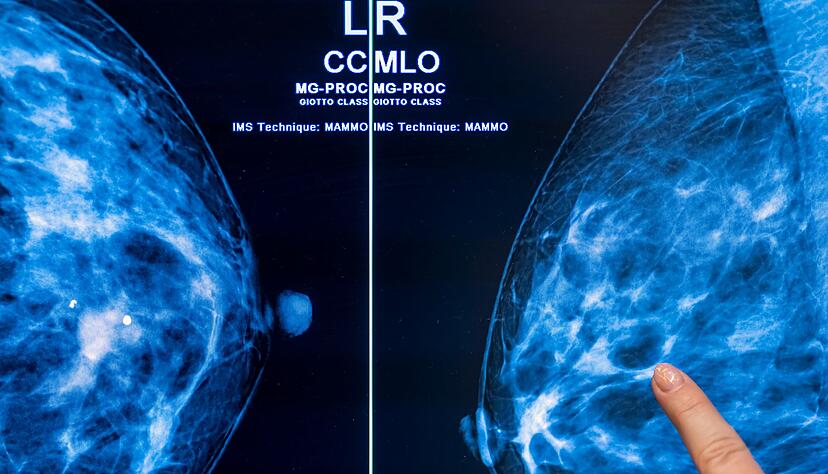

Röntgen-Untersuchung alle zwei Jahre

Im Zuge des Programms können Frauen im Alter von 50 bis 75 Jahren alle zwei Jahre eine Röntgen-Untersuchung der Brust zur Früherkennung in Anspruch nehmen. Bundesweit gibt es laut BfS 95 zertifizierte Screening-Zentren. Frauen, bei denen Symptome bestehen oder ein Verdacht auf Brustkrebs vorliegt, erhalten Mammografien zudem im Rahmen der allgemeinen Versorgung. Der Effekt dieser Untersuchungen wurde in der Studie nicht untersucht.